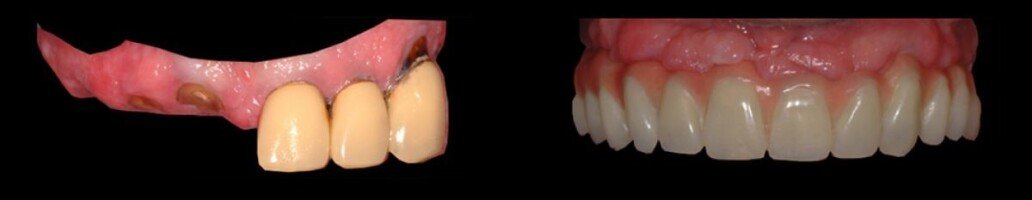

In questo caso si è reso necessario il rialzo del seno mascellare bilaterale, per la ricostruzione dei tessuti duri (osso) e dei tessuti molli (gengiva). La paziente ha portato 25 anni una protesi incongrua, questo le ha provocato la perdita di tanto osso. Con la tecnologia CAD-CAM, è possibile ricostruire le protesi, partendo da un disegno al computer, e poi produrla attraverso una macchina che costruisce in 3D il pezzo in zirconio o altro materiale. Il tecnico di laboratorio provvede poi a personalizzare con la porcellana estetica.

Prima

Dopo